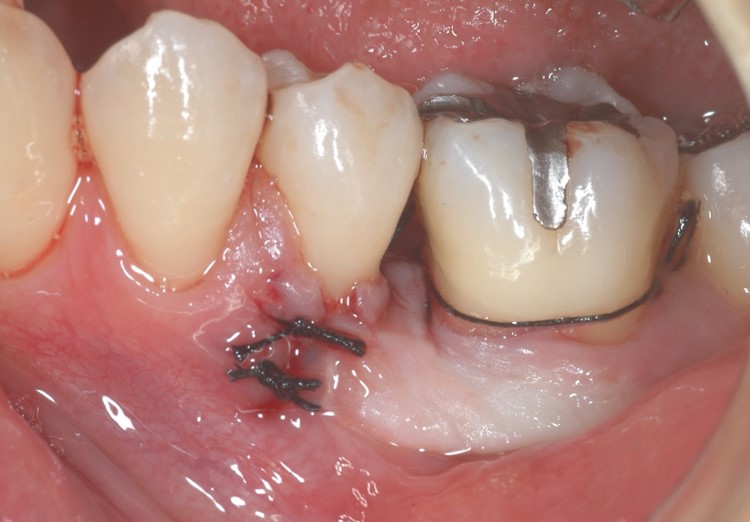

GTR膜の上に元の歯肉を戻して縫合しました(下写真)。